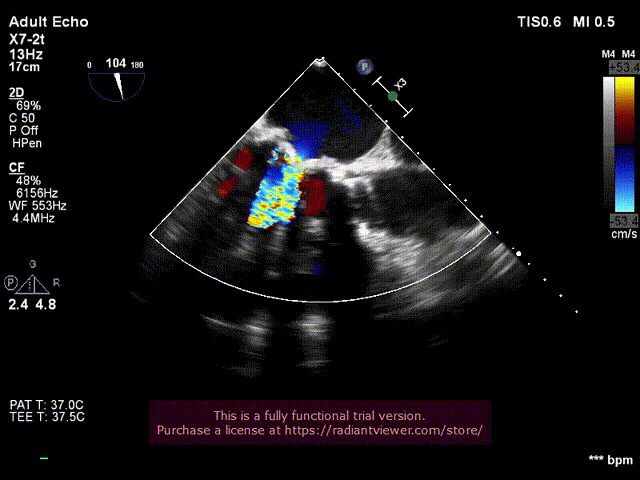

6.经食道超声评估主动脉瓣位SAPIEN 3植入

位置良好,瓣叶运动良好,无反流

10. 双瓣植入后左室造影与主动脉根部造影

双瓣SAPIEN 3瓣膜植入后主动脉根部造影

二尖瓣位和主动脉瓣位SAPIEN 3瓣膜功能良好

无心包积液